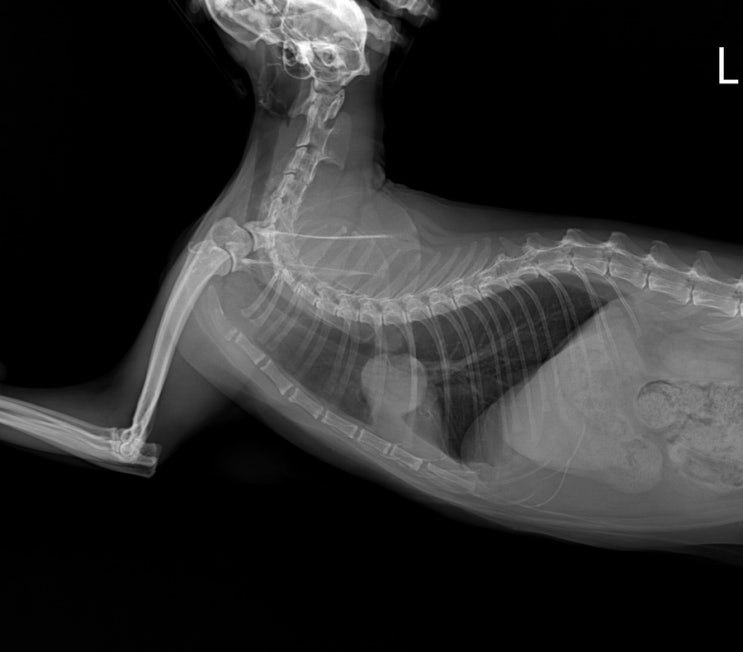

[초코이야기] 고양이 폐종양? 폐농양? - 9 (초코 최종 추정 진단은 폐농양/염증 + 인투바이오 펫 모발검사)

초코이야기 - 1 초코이야기 - 8 오랜만에 간 검사하러 간 초코 지난 번 검사 결과는 매우 작아졌었다. 2024...